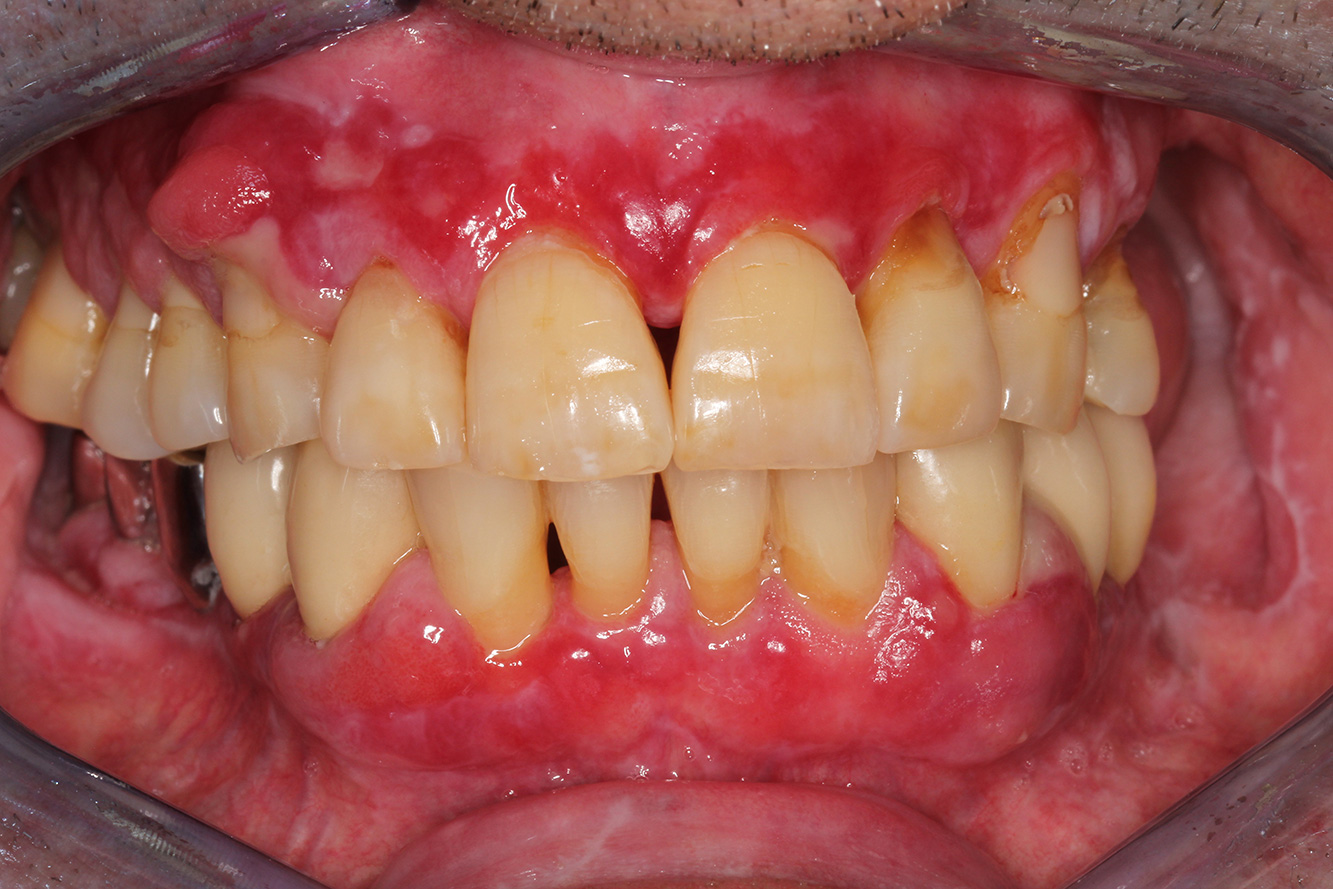

Paciente sana con enfermedad periodontal previa

La paciente de 68 años no tiene enfermedades previas relevantes de la salud general ni toma medicación; sus hábitos alimentarios tampoco suponen un riesgo especial. La paciente tiene dos implantes (tercer cuadrante, desde hace cinco años) y una enfermedad previa periodontal (periodontitis en etapa IV, grado B) con pérdida dental. Actualmente las condiciones periodontales son estables, pero la periodontitis aumenta de manera determinante las complicaciones biológicas cuando se realizan implantes y puede ocasionar la pérdida de un implante (21). Para la sesión de profilaxis se hacen cuatro recomendaciones. más información